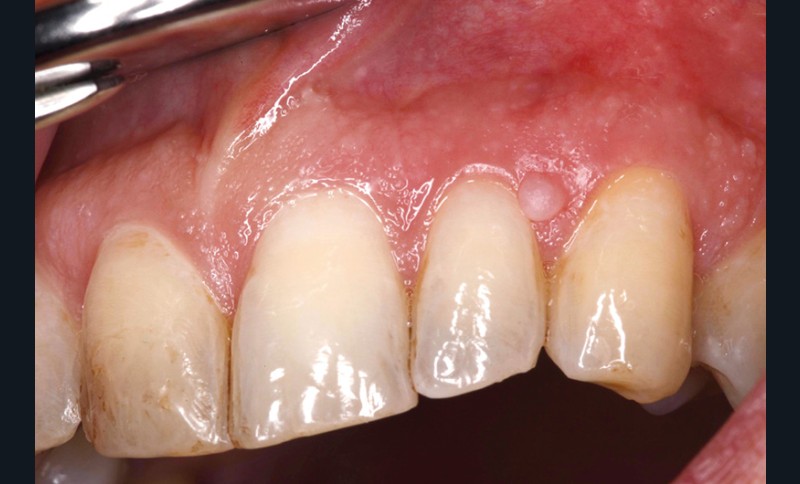

Examen clinique. La muqueuse buccale avait un aspect légèrement érythémateux, plus particulièrement celle du voile et du plancher buccal antérieur. Il n’y avait pas de mélanose tabagique, mais on observait la présence de pigment liée au tabagisme sur les dents. La lésion était constituée par un nodule ferme, de couleur rose pâle, pseudo-pédiculé, de 2 mm de diamètre, dont la base d’implantation n’était pas située directement sur le bord libre de la gencive.

Examen paraclinique. La lésion a été excisée et l’examen histopathologique de la pièce d’exérèse a montré que la tumeur était constituée par un tissu conjonctif fibreux dense, contenant quelques petits vaisseaux. Elle était revêtue par un épithélium malpighien discrètement orthokératosique, avec par endroits présence d’une fine granulose ; les crêtes épithéliales étaient élargies. Il s’agissait donc d’une petite épulis fibreuse.